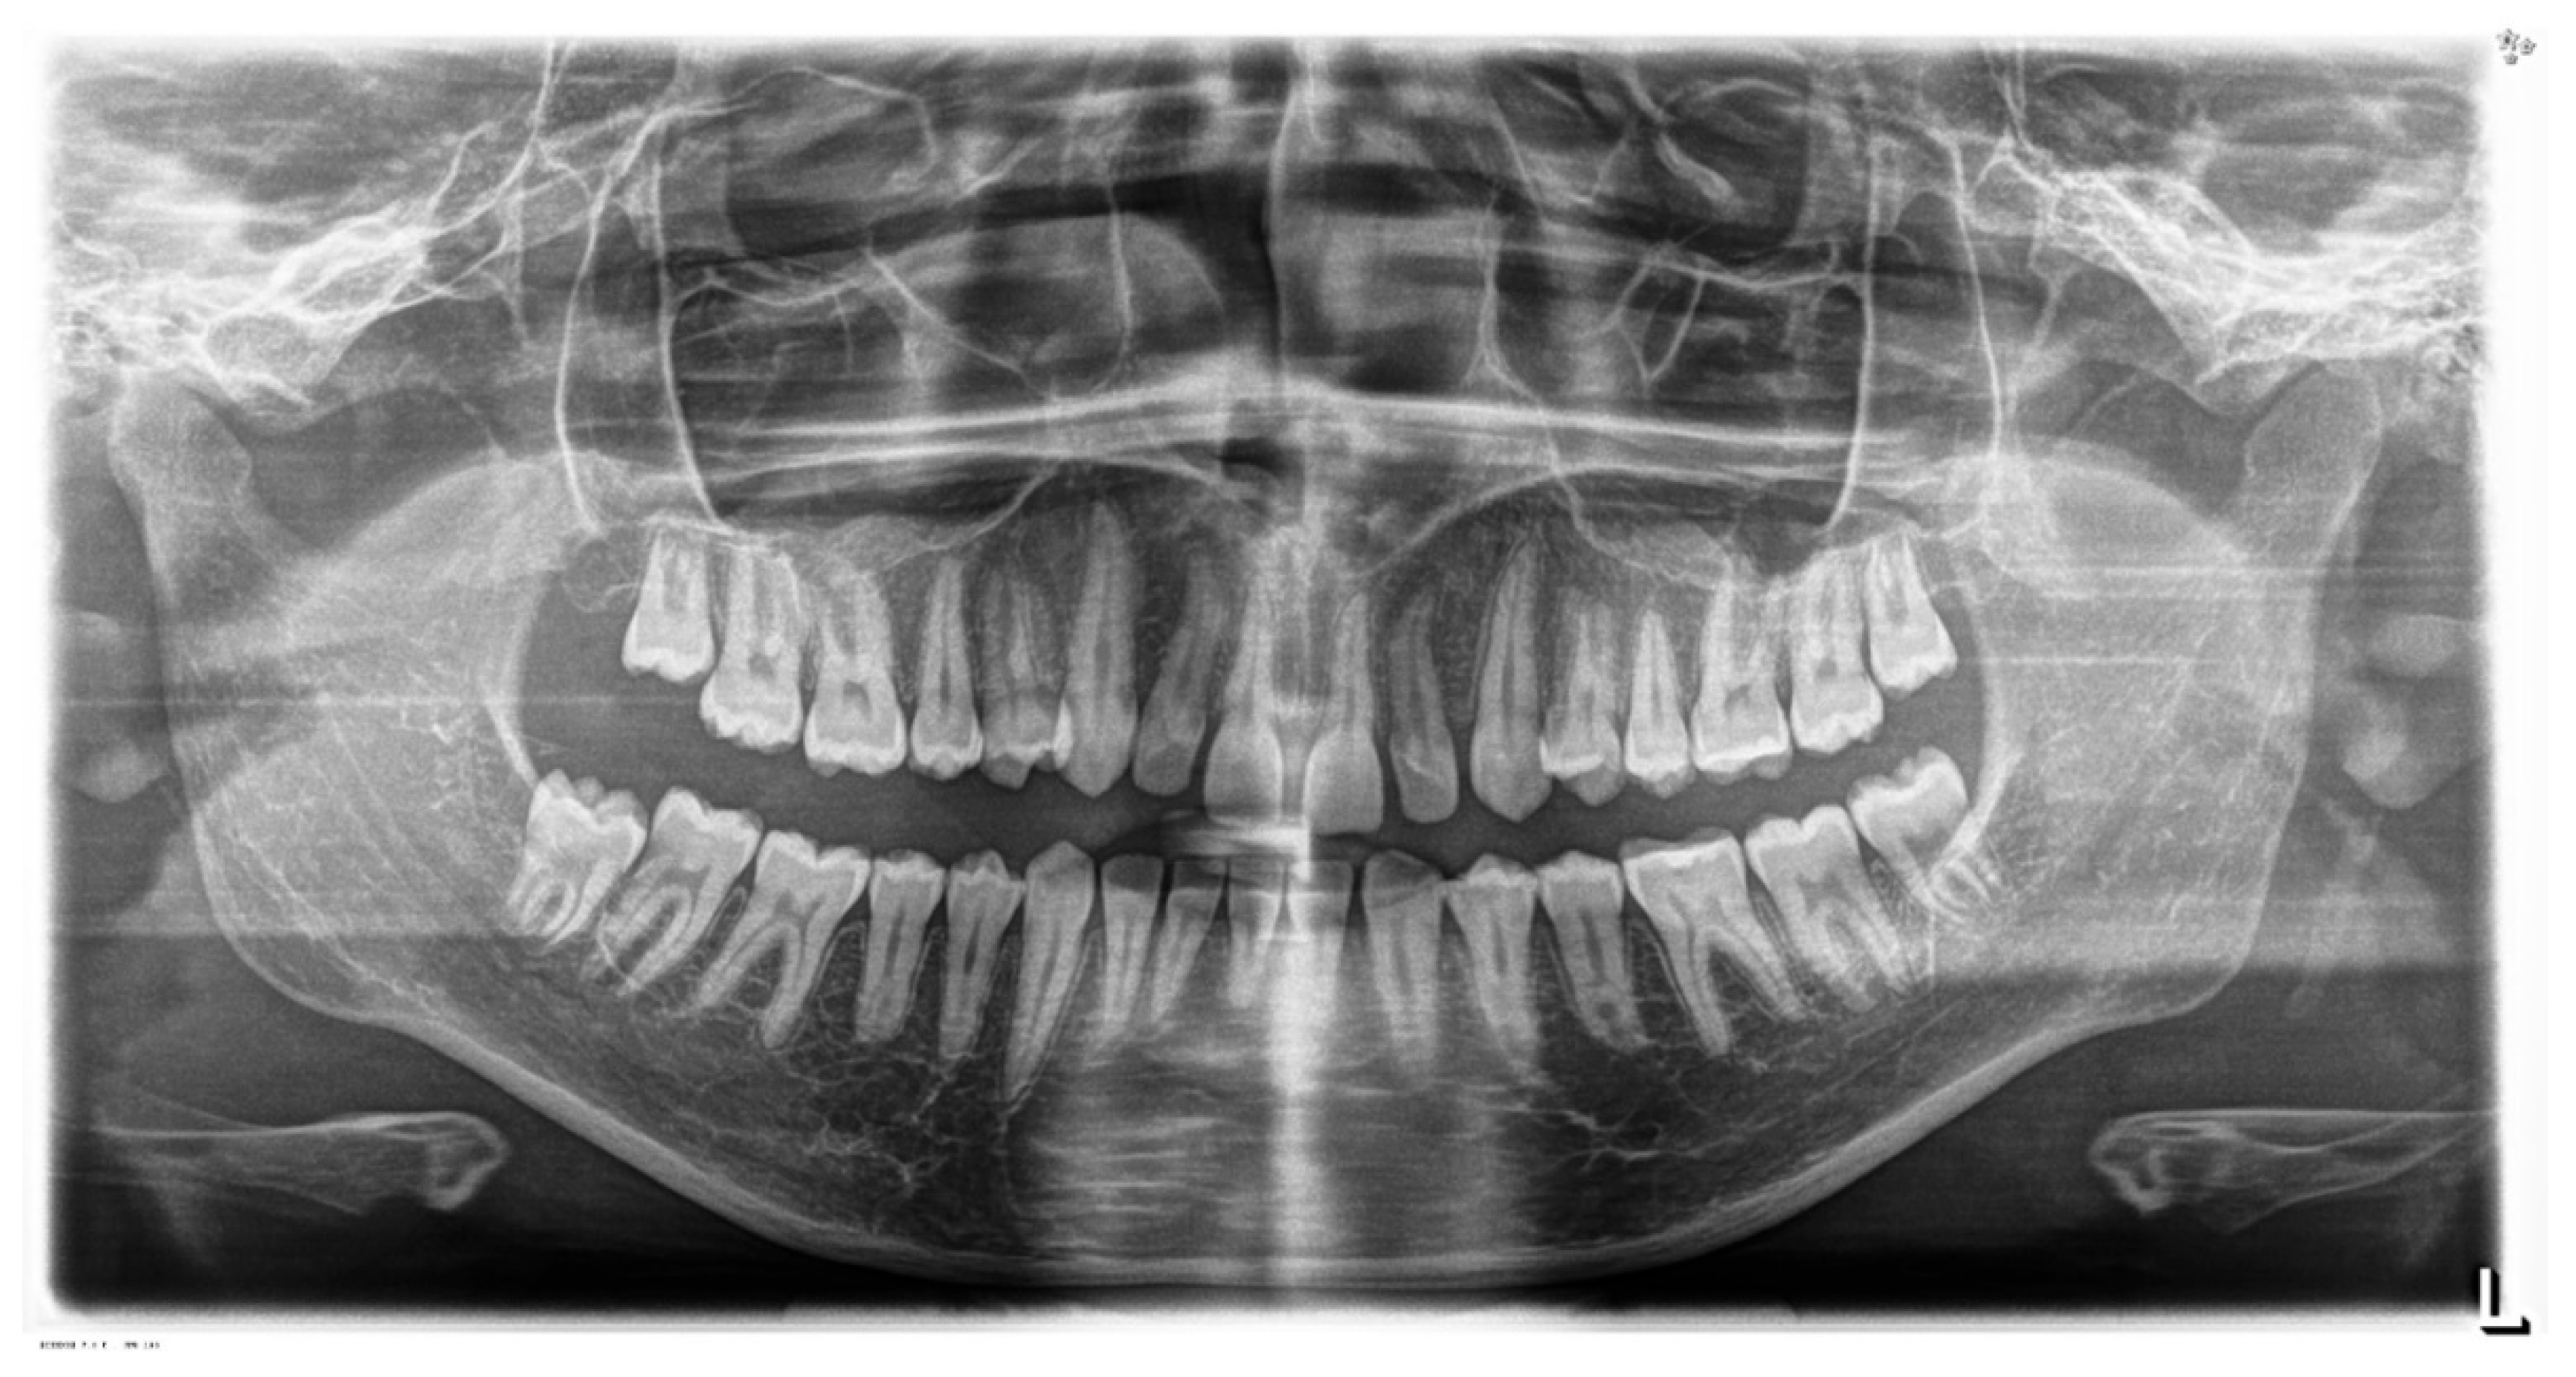

2.1. Diagnosis and Aetiology

2.3. Treatment Progress